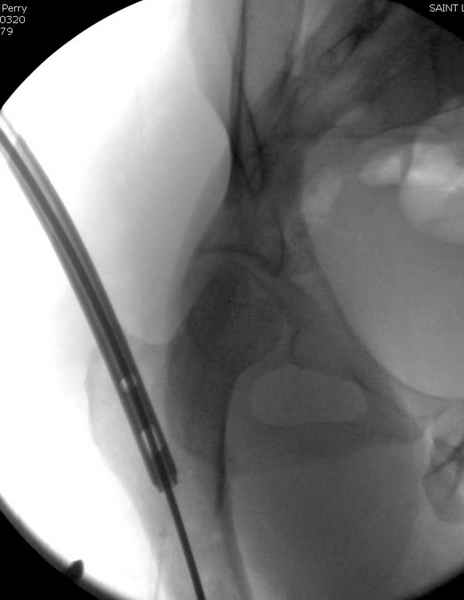

Как раз недавно у меня был примерный случай: больному 36 лет, поступил ночью, травма в результате мотоциклетной аварии, кроме чрезвертельного и спирального перелома левого бедра имеется переломы костей предплечья с этой же стороны. Скелетное вытяжение, а на следующий день больной про оперирован на ортопедическом столе с дистракцией. Чтобы не расколоть чрезвертельный перелом провели временную спицу ближе к переднему кортексу, из малого разреза костодержатель для репозиции, а фиксацию провели антиградным штифтом. Этапы операции на снимках.

Джолдас Кульджанов